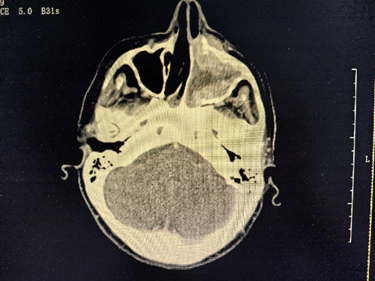

عندما أُدخلت ماكا إلى المستشفى لأول مرة، كان تجويف أنفها مسدودًا بالكامل تقريبًا بسبب الورم. وقد غزا الورم البلعوم الأنفي والجيب الغربالي الأيسر والجيب الفكي على نطاق واسع، مع تدمير موضعي للعظام المحيطة بها. وظهرت عدة عقد ليمفاوية نقيلية في رقبتها، وارتفع مستوى مستضد السرطان الجنيني لديها بشكل ملحوظ. في مواجهة هذه الحالة المعقدة، بادر الطبيب المعالج الدكتور تشو غوي تشينغ على الفور بإجراء استشارة متعددة التخصصات.

△ قبل العلاج